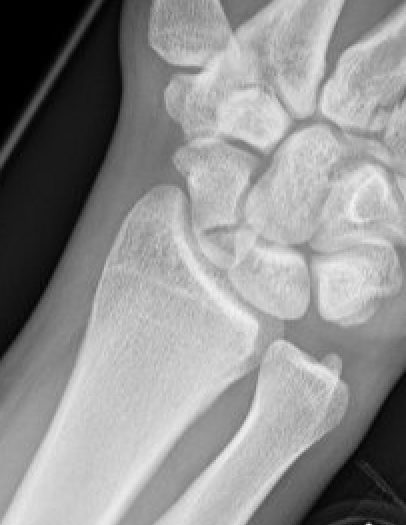

X-ray

5 images

- PA / lateral

- PA in 45° oblique pronation / PA 45o oblique supination

- PA in ulna deviation

Scaphoid waist fracture 1 mm displaced

Scaphoid fracture with significant displacement

Scaphoid proximal pole fracture